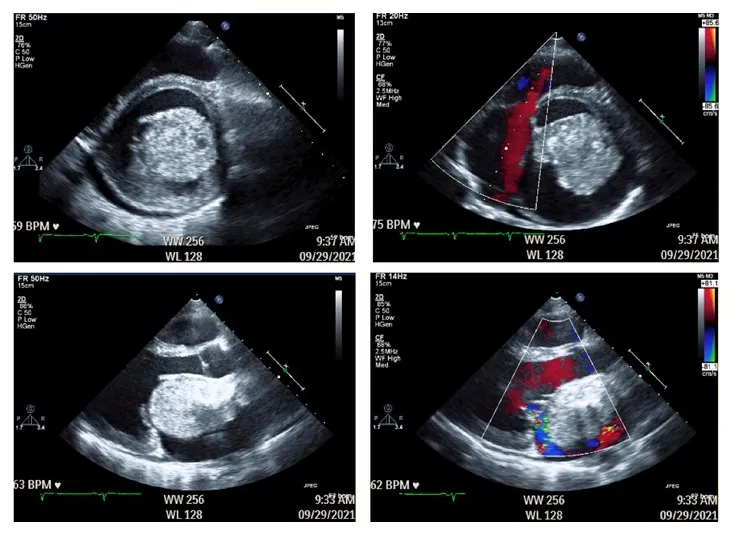

- Location: ~75% arise in the left atrium, often attached to the interatrial septum at the fossa ovalis.

- Obstructive: Mimics mitral stenosis (dyspnea, syncope). Positional symptoms are common. Auscultation may reveal a diastolic "tumor plop."

- Echocardiography (TTE/TEE) is the initial and primary diagnostic tool.